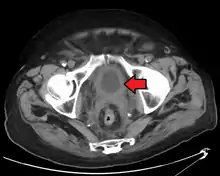

If invasive or high grade (includes carcinoma in situ) cancer is detected on TURBT, an MRI and/or CT scan of the abdomen and pelvis or urogram and CT chest or x-ray chest should be conducted for disease staging and to look for cancer spread (metastasis). Increase in alkaline phosphatase levels without evidence of liver disease should be evaluated for bone metastasis by a bone scan.[1] Although 18F-fluorodeoxyglucose (FDG)-positron emission tomography (PET)/CT has been explored as a viable method for staging, there is no consensus to support its role in routine clinical evaluations.[54]